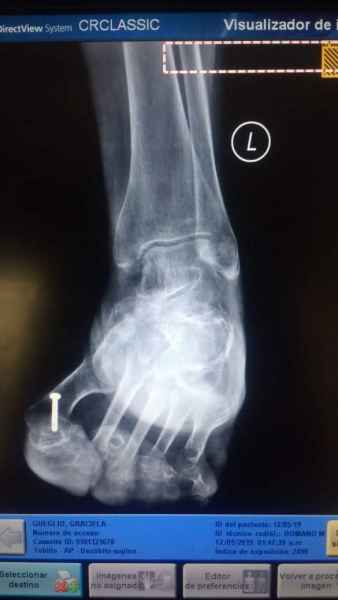

Tanto la estructura del pie como su funcionalismo que es la marcha, pueden ser asiento y manifestación respectivamente de alteraciones locales ó sistémicas, por lo que su cuidadoso examen resulta de extrema utilidad diagnóstica.

Dr. Juan Pablo Peralta, Ortepedia y Traumatología, Especialista en pies, Instituto Gamma